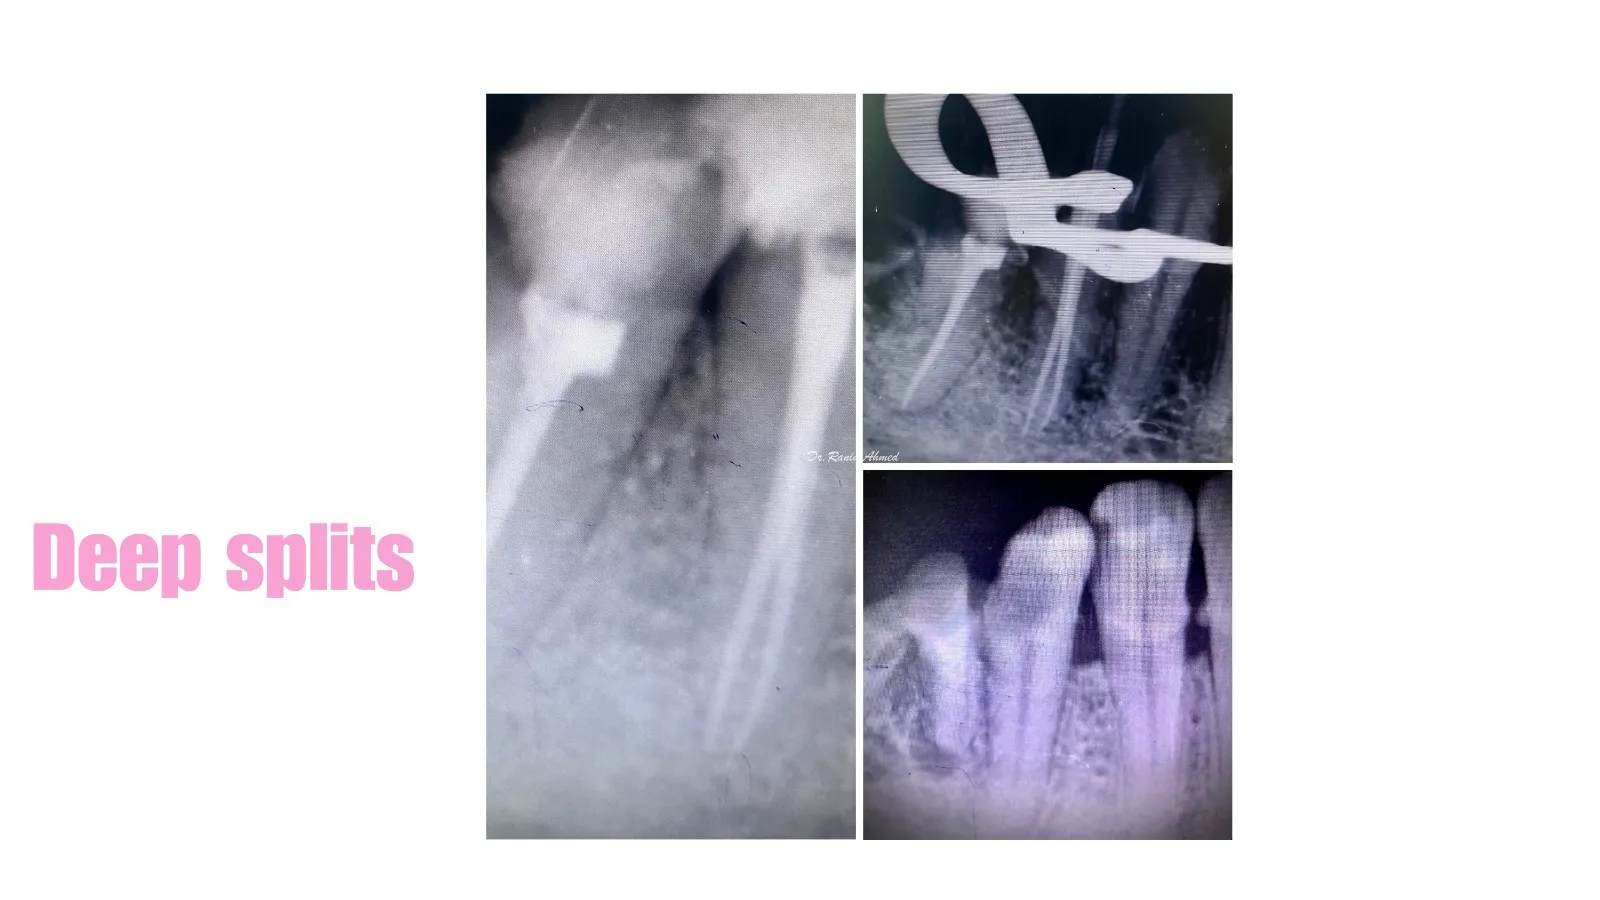

Endodontic Treatment